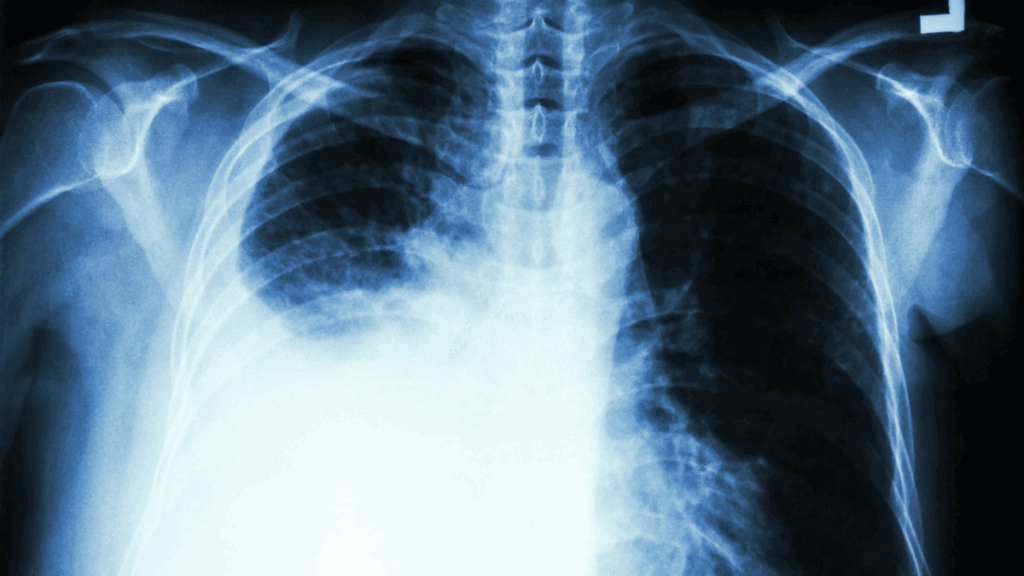

▲胸腔科医生揭白肺真相。

疫情升温,近日传出有许多人出现“白肺”症状,恐怖的名称让不少民众听了很害怕,胸腔重症科医师苏一峰表示,所谓的白肺,正确名称应该是肺炎重症或急性呼吸窘迫症,全世界的加护病房里面都会有,他自己手头上也有几个白肺患者,因此这并不是大陆才有的疾病。

苏一峰昨在脸书上分享,传大陆因为疫情出现了“白肺”,让许多人听了很恐慌,但其实所谓的白肺,正确名称应该是“肺炎重症”或“急性呼吸窘迫症”。而这个状况全世界的每家医院里面都会有,并不是只有大陆才有。

苏一峰表示,他自己手头上目前也有“白肺”患者,应该说,每家医院的加护病房里面应该都会有一大堆白肺的患者喔!而他应该也可以算是台湾的白肺专家了。